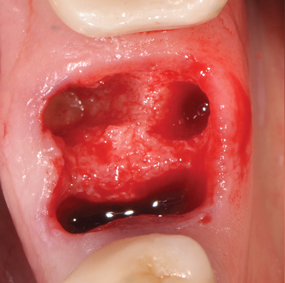

(1.) This series of clinical images illustrates the use of an implant with well-defi ned

threads that improve lateral bone engagement. In a multirooted extraction socket where there are large voids, this can help to achieve initial implant stability.

Figure 1

(2.) This series of clinical images illustrates the use of an implant with well-defi ned

Figure 2

(3.) This series of clinical images illustrates the use of an implant with well-defi ned

Figure 3

(4.) This series of clinical images illustrates the use of an implant with well-defi ned

Figure 4